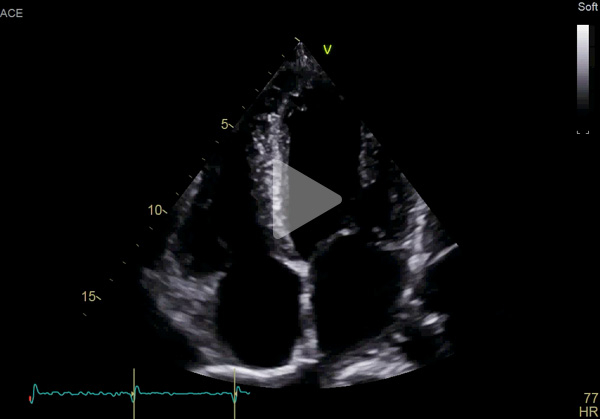

ETT :

- Hypertrophie ventriculaire gauche à prédominance septale (SIVd 12 mm, PPVG 12 mm) sans obstruction de repos, de fonction systolique conservée à 60 % en Simpson biplan. Cinétique homogène, SLG altéré à - 16 % en cocarde

- Profil mitral restrictif

- VD fin de bonne fonction longitudinale

- Pas de dilatation du massif atrial

- Pas de valvulopathie mitroaortique significative. Aorte ascendante non dilatée

- Veine cave inférieure fine respirante. Péricarde sec

Vidéo 1 : PSGA